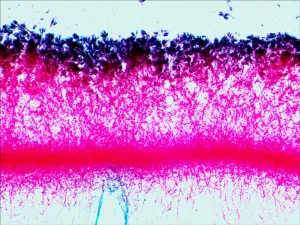

Примеры слайдов под микроскопом смотрите в галерее фотографий, а также в обзоре «Наборы готовых микропрепаратов Levenhuk» на сайте levenhuk.ru.